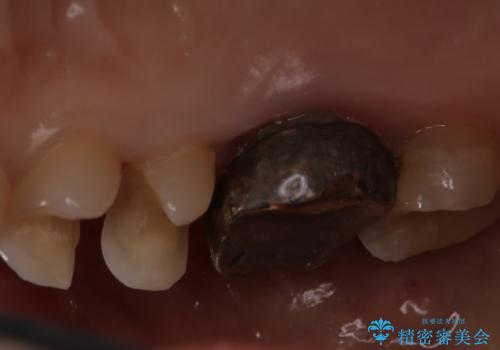

歯の間に食べ物がよく挟まるのを治したい

- 右上4、5間にフロスのひっかかりがあり、レントゲンから隣接面う蝕を確認しました。う蝕除去後は両歯にCADCAMインレーをセットしています。

歯の隣接面を正確に合わせることによって、物が詰まりにくく、再びう蝕になる確率を下げてくれます。